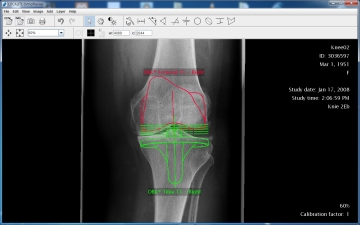

LOCALITE OrthoPlanner® - Digital prosthesis planning

The LOCALITE OrthoPlanner is a software designed to plan and fit endoprostheses based on digital X-ray images. It provides the possibility to plan endoprostheses of any kind and from all manufacturers. Angles, distances and sizes can be measured accurately. With the LOCALITE OrthoPlanner X-ray film expression and transparent plastic templates become unnecessary and the planning result can be archived digitally.